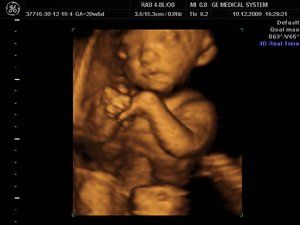

4D image of 29 weeks pregnancy, multiple anomalies: Clinch hand, omphalocoele, single atrium

Title of image: Clinch Hand

Description of image: 4D image of 29 weeks pregnancy, multiple anomalies: Clinch hand, omphalocoele, single atrium